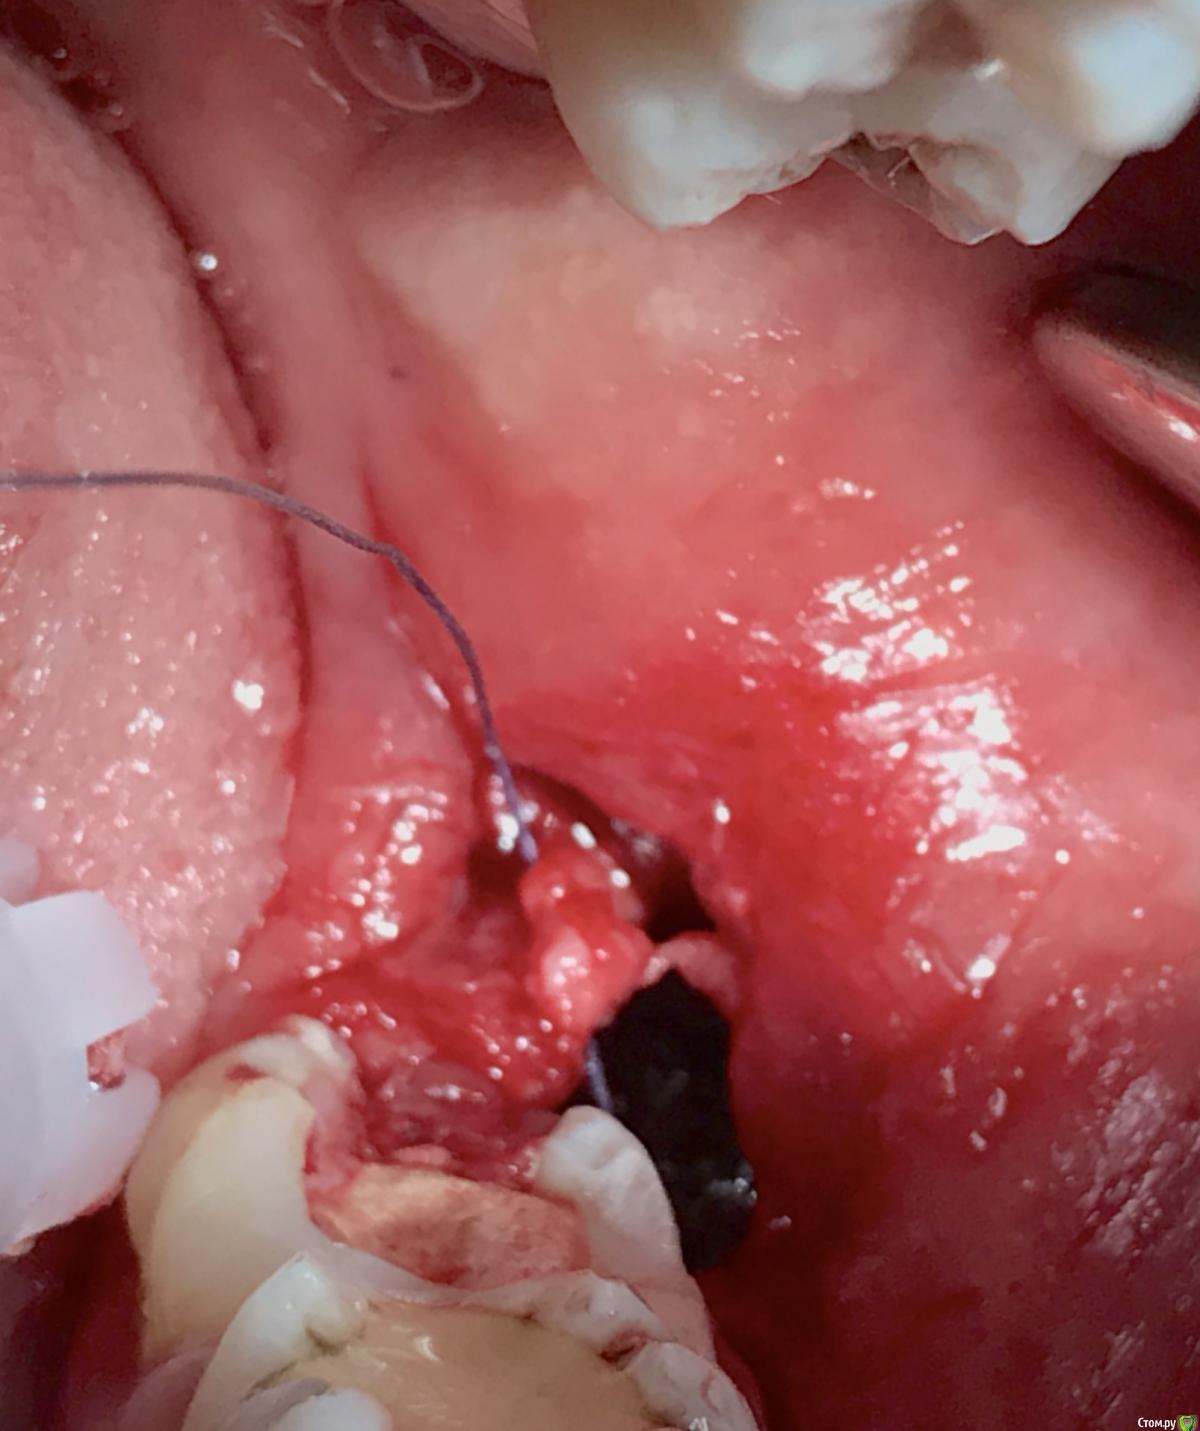

колесников Опубликовано 26 марта, 2017 Автор Поделиться Опубликовано 26 марта, 2017 (изменено) Вид через неделю. Швы удалены. Пациент как ни странно жив. Боли не испытывал ,3 дня был отек. Снимок "до". Изменено 26 марта, 2017 пользователем колесников Ссылка на комментарий